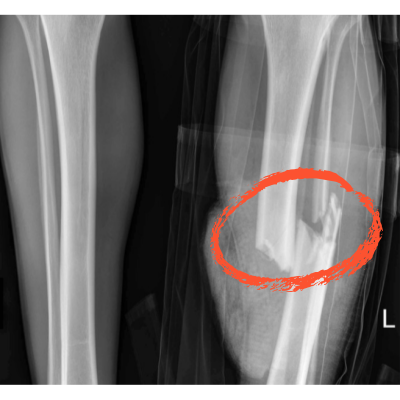

그래서 “부러진 뼈도 붙는다?”는 표현은 과장이라기보다, 그만큼 뼈가 잘 회복될 수 있는 환경을 만들어준다는 의미입니다.

실제로 골절 회복이나 골밀도 관리에서 비타민 K 섭취가 중요하다고 강조되는 이유도 바로 이 지점입니다.